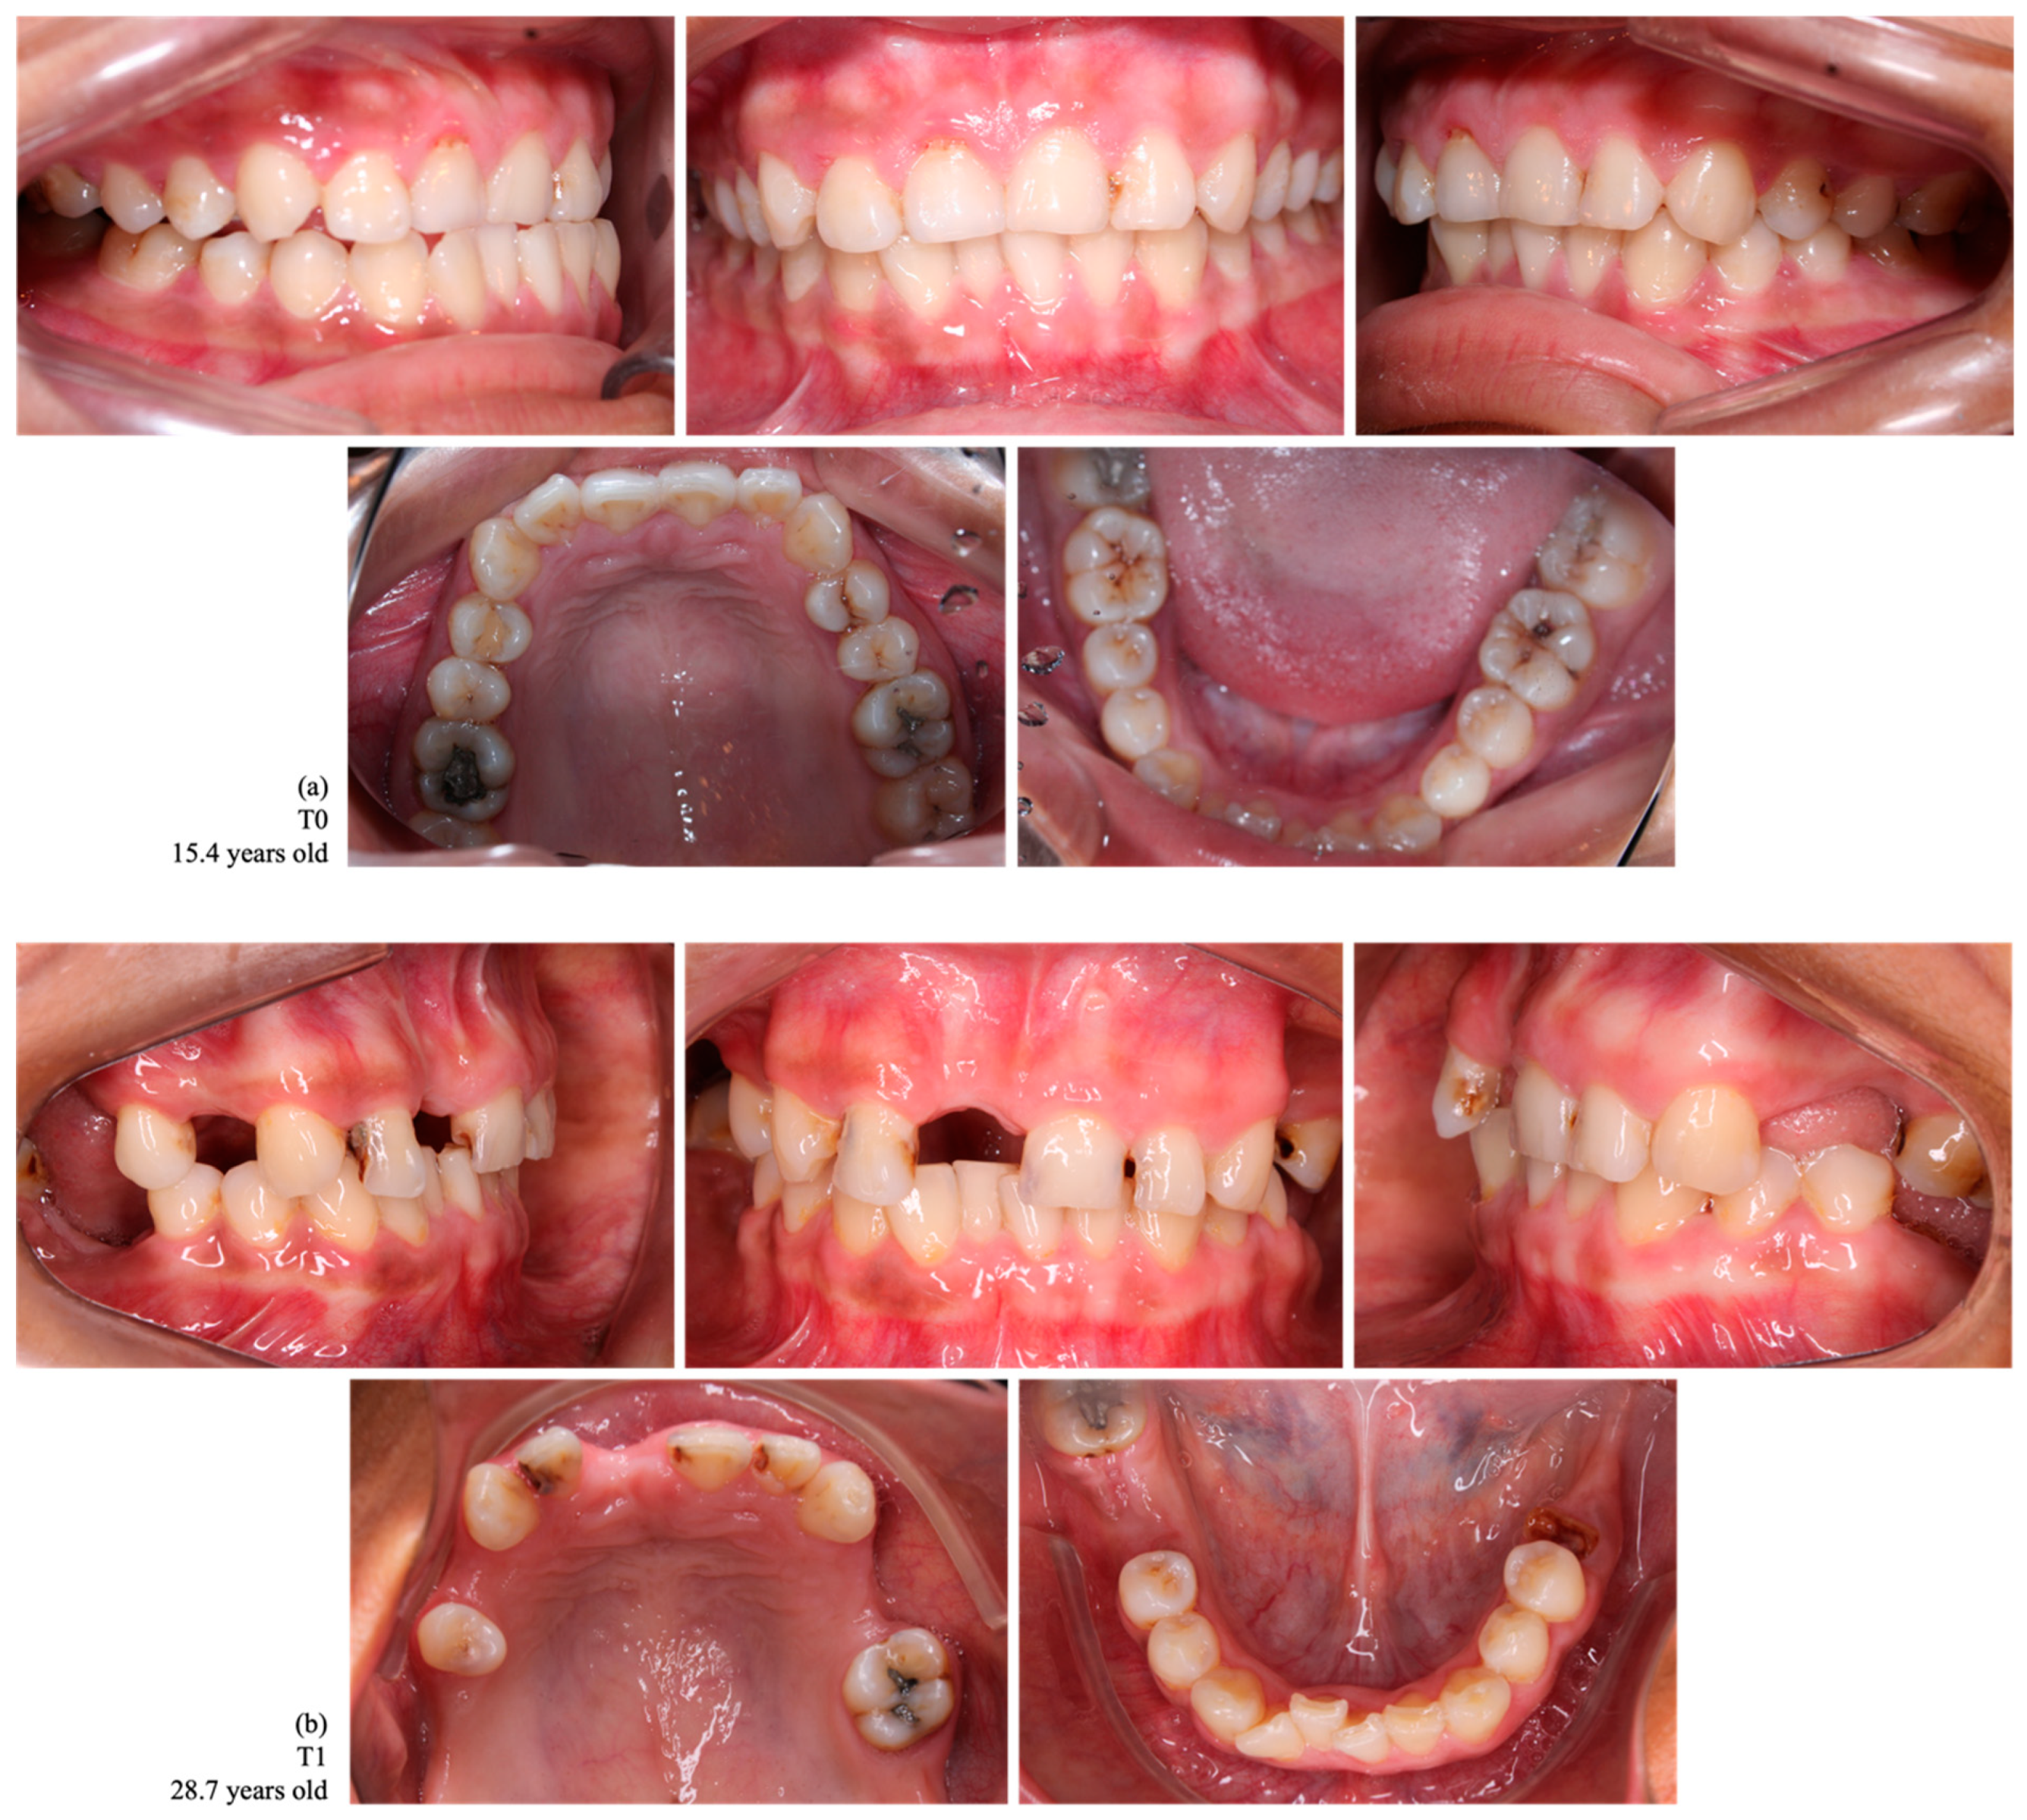

Figure 2.

Intraoral photographs of dental occlusion of a female indigenous participant, a habitant of the Assurini village, with no tooth loss at T0 (a) and with a loss of 10 permanent teeth at T1 (1.7, 1.6, 1.4, 1.1, 2.4, 2.5, 2.7, 3.7, 3.6, and 4.6) (b).